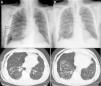

Presentamos el caso de un varón de 67 años con antecedentes de hidroneumotórax secundario a contusión pulmonar y neumotórax (N) espontáneo, diagnosticado de FPI, (subtipo síndrome combinado fibrosis/enfisema) según criterios clínico-radiológico-funcionales ATS/ERS 20111, tratado con pirfenidona. Consulta por clínica de dolor torácico, disnea brusca, con uso de músculos respiratorios accesorios, abolición del murmullo vesicular en hemitórax derecho y radiografía compatible con N a tensión (fig. 1A). Tras la colocación de drenaje endotorácico (DET) es trasladado a planta de hospitalización, objetivándose cámara pleural con fuga aérea (FA) persistente, a pesar de DET en 3 ocasiones (2 de ellos calibre fino, —8 y 10 F— y otro grueso —24 F—), sin resolución del N.

Se desestima la cirugía, ante el elevado riesgo quirúrgico por su enfermedad parenquimatosa, practicándose fibrobroncoscopia flexible (FF) el día 21 de ingreso mediante sedación profunda (paciente en posición semi-sentado con DET de 24G en hemitórax derecho con sello de agua que permitía objetivar la ausencia/presencia de FA), sin encontrar alteraciones endoscópicas en el árbol bronquial derecho. Se accedió al bronquio subsegmentario (BS) lateral del bronquio correspondiente al lóbulo medio (origen sugestivo de localización, tras estudio detallado de la tomografía axial computarizada [TAC]), procediendo mediante catéter Fogarty® al colapso completo de dicho BS, revelando ausencia de FA. Se procedió a la instilación de 2ml de cianoacrilato endobronquial guiado por catéter telescopado, sin complicaciones inmediatas. Al término de la FF, existía presencia de FA intermitente con progresiva desaparición, mostrando ausencia de N en la radiografía de tórax realizada, previa al alta hospitalaria, tras 16 días de la FF (fig. 1B).